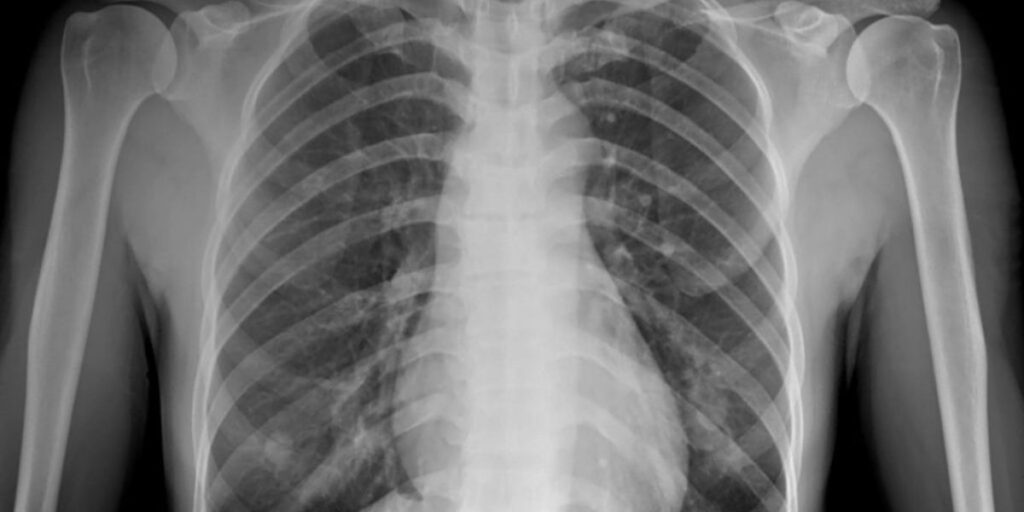

L’RX Torace è un esame che sfrutta le radiazioni ionizzanti per ottenere immagini dettagliate delle strutture interne del torace, inclusi i polmoni, il cuore, le ossa delle costole e il diaframma. Questo esame è essenziale per individuare anomalie e patologie come polmoniti, neoplasie, effusioni pleuriche e alterazioni cardiache. Grazie alla sua capacità di fornire immagini chiare e precise, l’RX Torace è uno strumento diagnostico indispensabile per i medici che desiderano valutare lo stato di salute del torace.

Durante l’esame, una piccola dose di radiazioni ionizzanti viene diretta attraverso il torace. I tessuti con densità diversa, come le ossa e i polmoni, assorbono le radiazioni in modo differente, creando così un’immagine dettagliata che il medico radiologo utilizza per analizzare lo stato di salute del paziente. I tessuti più densi, come il cuore e le ossa, appariranno più chiari, mentre i tessuti meno densi, come i polmoni, risulteranno più scuri. Al Poliambulatorio S-Medical Group di Sora, vengono adottate tutte le misure di sicurezza per ridurre al minimo l’esposizione alle radiazioni, garantendo la massima protezione del paziente.

L’RX Torace consente di visualizzare con chiarezza diverse strutture interne del torace. È possibile identificare anomalie nei polmoni, come la presenza di infezioni o tumori, valutare le dimensioni e la forma del cuore e rilevare effusioni di liquidi nella cavità pleurica. Inoltre, l’esame può rivelare fratture costali e altre alterazioni ossee, rendendolo uno strumento versatile per la diagnosi di numerose condizioni patologiche.